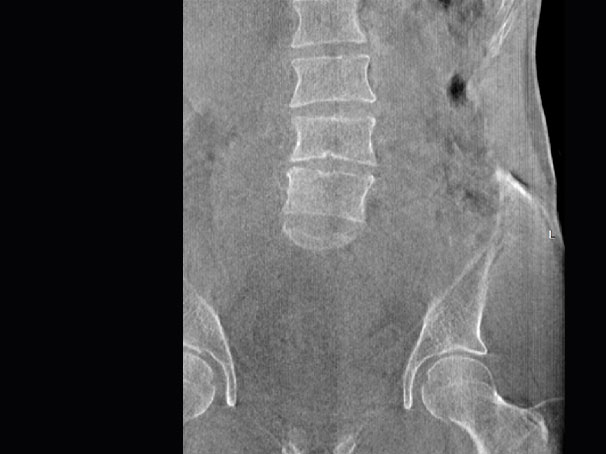

髋关节

精准诊断

手术方案规划

术后随访